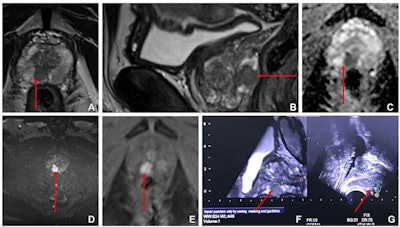

The authors conducted a study that included 582 patients with suspected prostate cancer who underwent multiparametric MRI between January 2015 and August 2020. Of these, 413 had a PI-RADS score of at least 3 (intermediate -- and equivocal -- disease risk) and were randomized into either an intervention group that underwent ultrasound and MRI fusion-targeted biopsies with systematic random prostate biopsies (207, or 50.1%) or a control group which underwent systematic random biopsies alone (206, or 49.9%). The men underwent biopsy within a week after the multiparametric MRI exam.